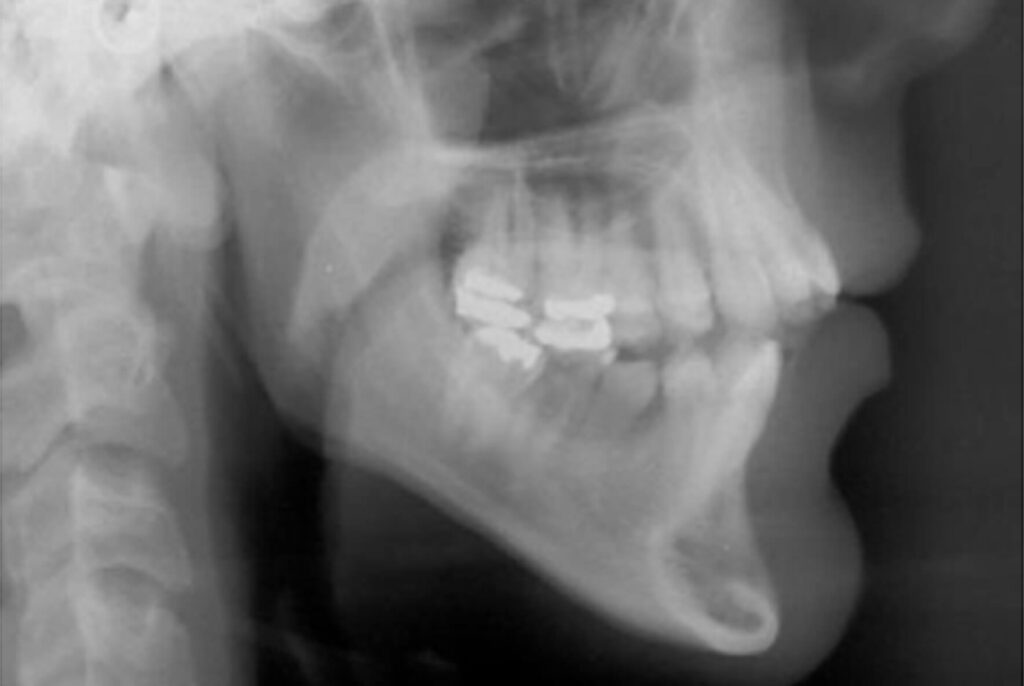

Na radiografia panorâmica inicial foi observada a ausência dos dentes 35 e 36; presença de restauração dos molares superiores e inferiores; e dente 45 em infraoclusão e com grande angulação para mesial. As estruturas adjacentes aos dentes apresentavam aspecto de normalidade (Figura 3).